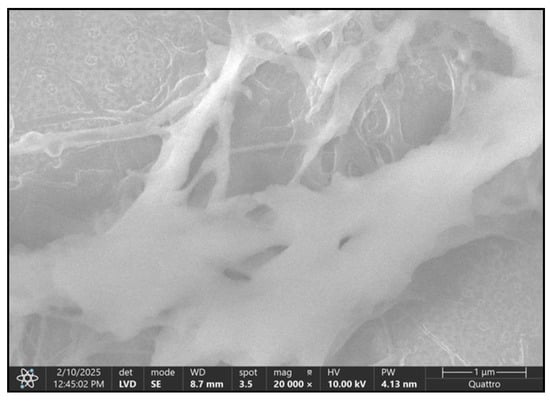

3.3. Results of SEM Study

- The fineness of normal vascularization is highlighted, which emphasizes the intimate relationship between bone and the vascular system, which is essential for bone nutrition and regeneration (Figure 10, control).